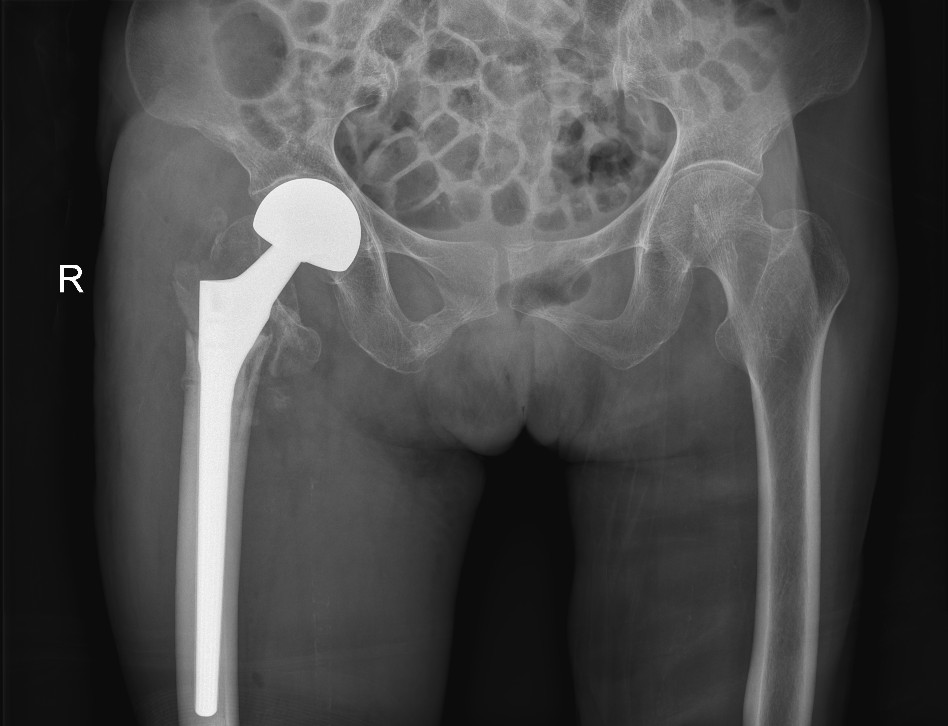

手术后X光片显示情况

4月10日,脊柱关节骨病外科团队为林阿婆实施人工股骨头置换手术。经过术前充分准备,手术过程中的紧密配合,手术顺利完成!术后,林阿婆出现了血氧饱和度较低等情况。脊柱关节骨病外科团队立即给予面罩吸氧,同时进行抽血检查,血象结果提示,林阿婆血红蛋白与红细胞较低,携氧能力低才会出现此症状,随后医护人员马上联系输血科给其进行紧急输血治疗。经过及时救治,林阿婆生命征最终恢复稳定。